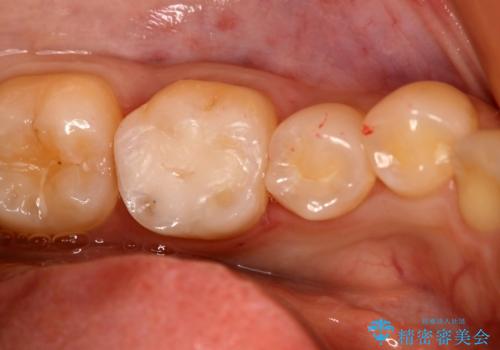

- 左上奥歯の銀歯のやり変えを希望された患者様です。

白くしたいとの事だったので形態・切削量を考慮し、セラミックインレーでの治療を計画しました。